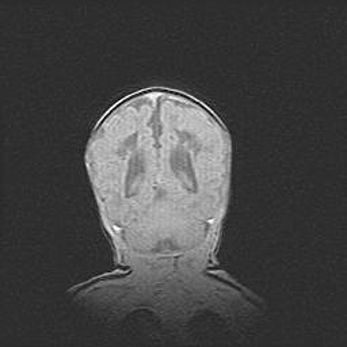

Множественные кисты обоих полушарий головного мозга, наибольшая из них в правой затылочной области. Ассиметричная атрофическая гидроцефалия.

Возраст: 7 месяцев

Вес: 5660 г

Пол: мужской

Окружность головы: 41,5 см

Срок гестации: 28-29 недель

Кисты головного мозга развиваются в результате многоочаговых некрозов вещества мозга и возникают вследствие перенесенной перинатальной инфекции, менингитов, энцефалитов, асфиксии, родовой травмы, расстройств мозгового кровообращения различного генеза. Образованию кист в веществе головного мозга плодов и новорожденных способствуют такие факторы, как высокое содержание в нем воды, недостаточная (или отсутствие) миелинизация и слабая астроглиальная реакция на повреждение.

Кисты могут сочетаться с гидроцефалией и другими поражениями головного мозга.